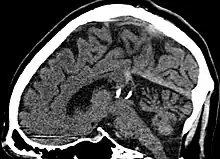

![]() | |

| Calcified cyst of pineal gland in CT. Sagittal MPR. |